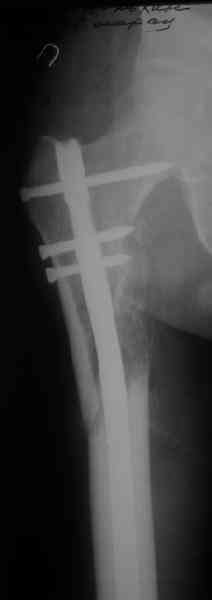

Судя по уровню перелома, винты в шейку избыточны, подойдет и диафизарный гвоздь. Все, что нужно, это тиски и труба. Загнуть сразу ниже отверстий градусов на 8-10, и вся недолга. Последние годы у нас это рутинная практика. Предызогнутые еще с завода гвозди неудобны тем, что они уже правый-левый.

Согласен, что закрытый реостеосинтез с рассверливанием и коррекцией оси - это то, что надо. Мы бы ввели в центральный отломок статических 2-3 винта, и один динамический винт в дистальном отломке.

Вот несколько. С тисками и трубой на днях сделаем.